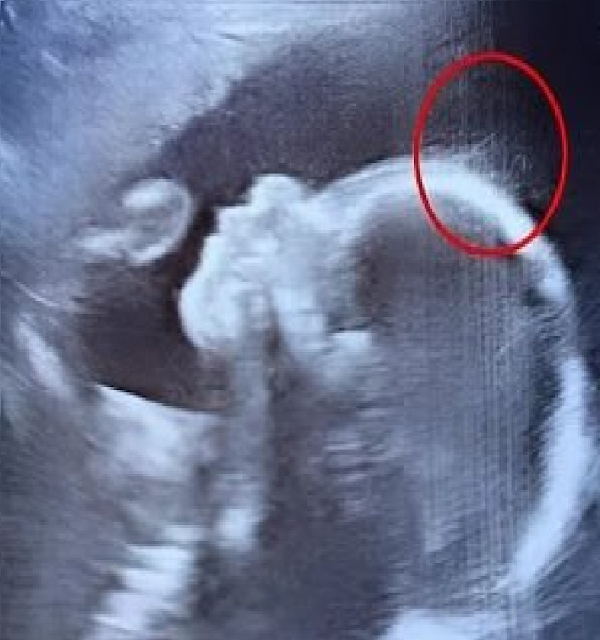

“Jessica had gone in for what she thought was just another routine ultrasound. Like most expectant mothers, she hoped to see the little flutters of her baby’s heartbeat on the screen, a moment of reassurance that everything was fine. But what the doctors saw that day left everyone in the room speechless.”